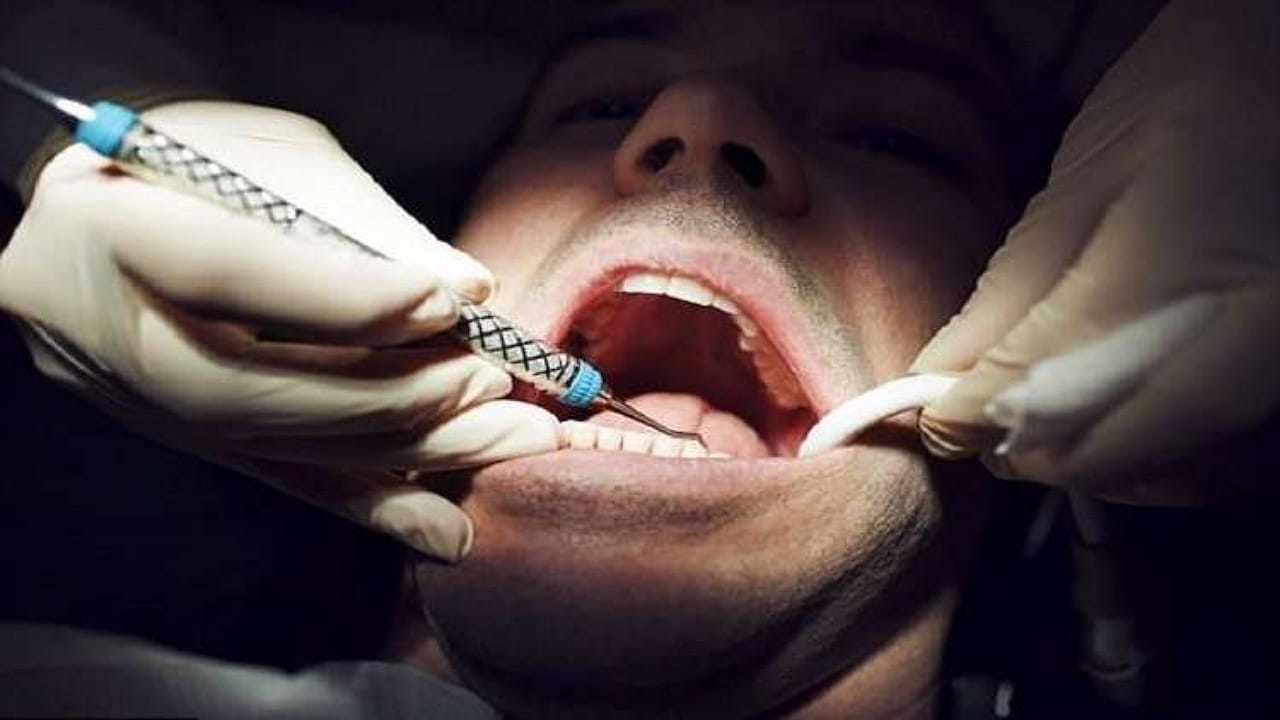

واقعة صادمة .. ذهب لعلاج أسنانه فعاد بمسمار في رأسه !

“طبيب أسنان” يوضح أنواع التقويم وأشكاله وخصائصه (فيديو)

“طبيب” يكشف أسباب نقص فرص العمل لأطباء الأسنان